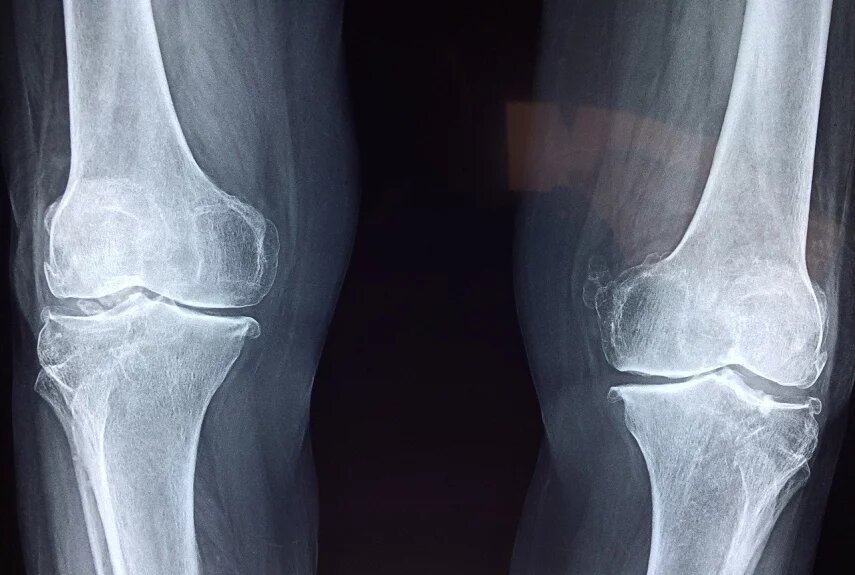

Почему болит сустав: главные отличия артроза от артрита

Артроз и артрит – самые распространенные болезни суставов. Они похожи, но появляются по разным причинам, отличаются их симптомы и методы лечения.

Общие отличия артроза и артрита

• Возраст. Артроз обычно встречается у людей старше 45 лет. Случаи появления болезни в более молодом возрасте связаны с травмами, пороками развития и тяжелыми хроническими заболеваниями. Артрит преимущественно поражает людей младше 40 лет, нередко диагностируется у детей.

• Тип течения. Артроз всегда с самого начала протекает хронически. Артрит чаще манифестирует остро, в последующем либо излечивается, либо переходит в хроническую форму.

• Скорость прогрессирования. Артроз прогрессирует медленно, тяжелые деформации и ограничения движений возникают спустя многие годы или даже десятилетия с момента начала болезни. При артрите изменения нарастают быстрее, хотя возможно и благоприятное течение.

• Распространенность. Артроз – это локальный процесс, поражается один сустав или небольшое количество суставов. Артрит часто захватывает много суставов, сочетается с изменениями со стороны внутренних органов.

Как отличить по симптомам

Общими симптомами артроза и артрита считаются боли, ощущение скованности, дискомфорт в начале движений, внешняя деформация и повышенная чувствительность сустава к физическим нагрузкам, погодным изменениям. Отличить одну болезнь от другой можно по следующим признакам.

• Начало и динамика болей. При артрозе боли нарастают постепенно: от незначительного дискомфорта до выраженного болевого синдрома проходят годы. При артрите боль появляется внезапно на фоне полного благополучия.

• Время появления болей. Для артроза характерна кратковременная стартовая боль, которая быстро исчезает при продолжении движений и снова появляется на фоне высокой нагрузки. Ночные боли возникают только на поздних стадиях. При артрите, напротив, сустав с самого начала больше болит во второй половине ночи. Боль дольше сохраняется после начала движений, утихает при разработке сустава.

• Местное воспаление. При артрите пораженные суставы отекают, становятся горячими на ощупь, кожа над ними краснеет. У пациентов с артрозом подобные симптомы появляются только в фазе обострения.

• Внешние изменения. На ранних стадиях артроза сустав выглядит нормально. У больных с артритом отчетливо видна припухлость, контуры сустава сглажены. На заключительном этапе в двух случаях формируются деформации.